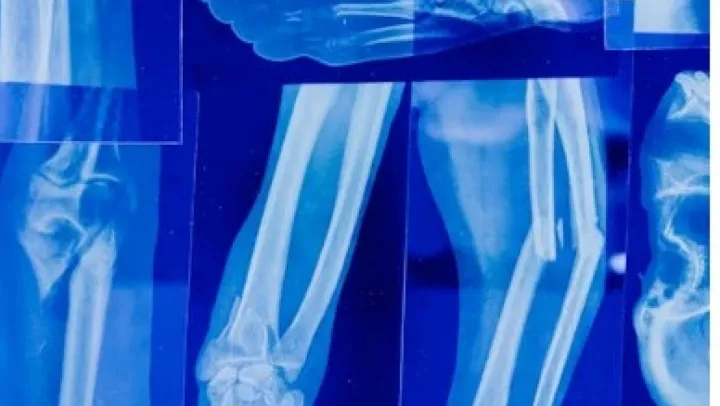

Vücuttaki eklemleri etkileyen artrit, iltihaplanma sonucu ortaya çıkan bir kas-iskelet sistemi hastalığı olarak biliniyor. Halk arasında 'eklem iltihabı' olarak da adlandırılan bu rahatsızlık, ağrı, şişlik, sertlik ve hareket kısıtlılığı gibi belirtilerle kendini gösteriyor. Uzmanlar, artritin tek bir hastalık olmadığını, aslında 100'den fazla farklı eklem rahatsızlığını kapsayan genel bir terim olduğunu belirtiyor. En yaygın görülen türleri arasında osteoartrit (kireçlenme) ve romatoid artrit (iltihaplı eklem romatizması) bulunuyor. Hastalığın nedeni genellikle yaş, genetik faktörler, eklem yaralanmaları, fazla kilo ve bağışıklık sistemi bozuklukları olarak sıralanıyor. Tedavi sürecinde erken tanı büyük önem taşıyor. Artritin tamamen iyileşmesi mümkün olmasa da, ilaç tedavisi, fizik tedavi ve yaşam tarzı değişiklikleri ile hastalığın ilerlemesi yavaşlatılabiliyor. Uzmanlar, özellikle soğuk havalarda eklem ağrısı yaşayan kişilerin mutlaka bir doktora başvurmasını öneriyor. Düzenli egzersiz, dengeli beslenme ve kilo kontrolü ise artritten korunmada etkili yöntemler arasında gösteriliyor.